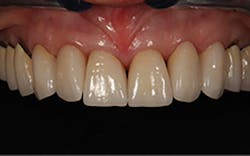

A 67-year-old female executive presented after becoming very self-conscious about the appearance of her anterior teeth (figure 1). During the consultation appointment, a thorough examination was performed, and scanned intraoral 3-D images and impressions (Trios, 3Shape) were obtained. Both arches and the bite registration were scanned (figure 2).

Figure 1: Preoperative retracted view of a female patient’s maxillary anterior teeth showing lingually positioned central incisors due to severe crowding of her arch